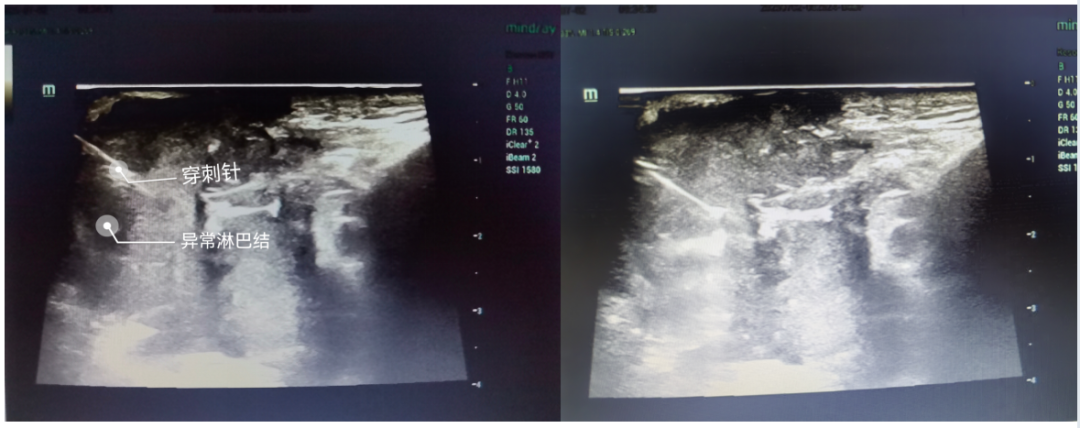

7月2日,德州市中医院特检科与外一科强强联合,成功完成医院首例介入超声引导下经皮穿刺淋巴结组织学活检术,填补了医院在该技术领域的空白,标志着精准诊疗水平再上新台阶!

77岁的患者张先生(化名)3个月前曾接受颈部淋巴结手术,但术后切口愈合不良,1个月前创口出现红肿、疼痛及周围水肿。为明确病因,医院多学科团队综合评估后,决定采用介入超声引导穿刺活检术。手术在超声实时精准引导下完成,全程安全高效,患者无不适感,成功获取淋巴结组织送检,为后续治疗提供了关键病理依据。